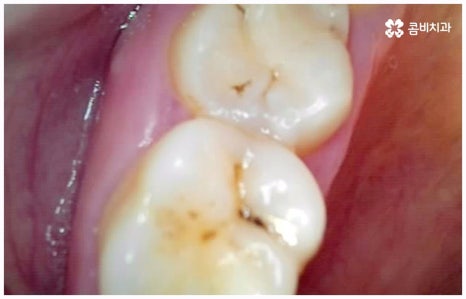

사람의 치아는 유치에서 영구치로 바뀌고 나면 다시 새롭게 나지 않기 때문에 만약 충치 등 구강 질환이나 노환, 외부 사고로 인해 치아를 잃게 되면 이를 대체해 줄 필요가 있습니다. 저작 기능을 담당하고 있기 때문에 치아가 없으면 매일 식사를 할 때 불편함이 크고 발음이 부정확해 질 수도 있으며 양치질을 할 때도 음식물 찌꺼기가 잘 끼는 등 위생 문제가 생길 가능성도 있어요. 또한 앞니 같이 잘 보이는 위치에 있는 치아를 상실하였을 경우 심미적으로도 자신감이 떨어질 수 있는데다 치아 상실 후 시간이 오래 지나도록 그대로 방치하게 되면 주변 치아들이 해당 부위 쪽으로 기울어지게 되고 잇몸뼈 역시 흡수가 일어나기 시작하기 때문에 옆 치아도 내려가면서 치열이 불규칙하게 바뀔 수 있습니다. 결국 심한 경우 상악과 하악의 불균형 및 안면비대칭까지 유발할 수 있기 때문에 치아가 빠졌을 때는 인공 치아를 통해 기능적 심미적인 대체를 해 줄 필요가 있는데요.

임플란트 종류 는 환자분들의 상황에 따라 달라지기 때문에 먼저 꼼꼼하게 정밀 검진을 받아보고 숙련된 의료진과 충분히 상담을 해 볼 필요가 있습니다. 환자분들의 치아 및 잇몸과 뼈의 상태, 전신 건강 등을 종합적으로 살펴보고 만약 필요하다면 선행 치료부터 받게 될 거예요. 선행 치료는 보통 임플란트 식립을 하게 된 치아 상실의 원인, 그리고 치아가 상실된지 얼마나 오랜 시간이 흘렀는지 여부에 따라 달라지는데 예를 들어 비교적 어린 나이에 큰 사고를 당해서 치아를 잃게 되었을 때 지체없이 바로 치과로 내원한 경우, 잇몸뼈가 건강하고 나이 등 회복력에 대한 기대치도 높은 편이며 다른 전신 질환, 상용약 등 잇몸에 지속적인 영향을 줄 만한 요소가 없다고 한다면 별다른 선행치료 없이 임플란트 종류 중 당일 심고 바로 임시 치아로 식사를 할 수 있는 원데이 임플란트를 통해 보다 빠르고 간편한 수복을 할 수 있어요.

비용이나 시간적인 부담이 만만치 않기 때문에 임플란트를 보다 오랜 기간 동안 건강하게 사용하려면 어떻게 해야 하는지 궁금해 하시는 분들이 많이 있으실 거예요. 임플란트 식립 성공률 및 지속률에 가장 크게 영향을 주는 것은 환자분들의 잇몸뼈 건강 상태 및 술자의 숙련도라고 할 수 있는데요. 예를 들어 구강 질환을 원인으로 한 병증이 심각하거나 치아를 상실한지 오랜 시간이 지나 잇몸뼈의 흡수가 많이 일어났기 때문에 높이와 밀도 등이 식립을 진행하기에 충분하지 않다면 뼈이식을 선행하여 기반부터 튼튼하게 보충해 줄 필요가 있어요. 또한 노화로 인해 상악동이 내려왔다면 상악동 거상술을 통해 공간을 확보해 주어야 하는데 이렇게 고난도 수술의 경우 다양한 임상 경험을 통해 풍부한 노하우와 뛰어난 기술력을 가지고 있는 의료진과 함께 하는 것이 무엇보다 중요하다고 할 수 있습니다.